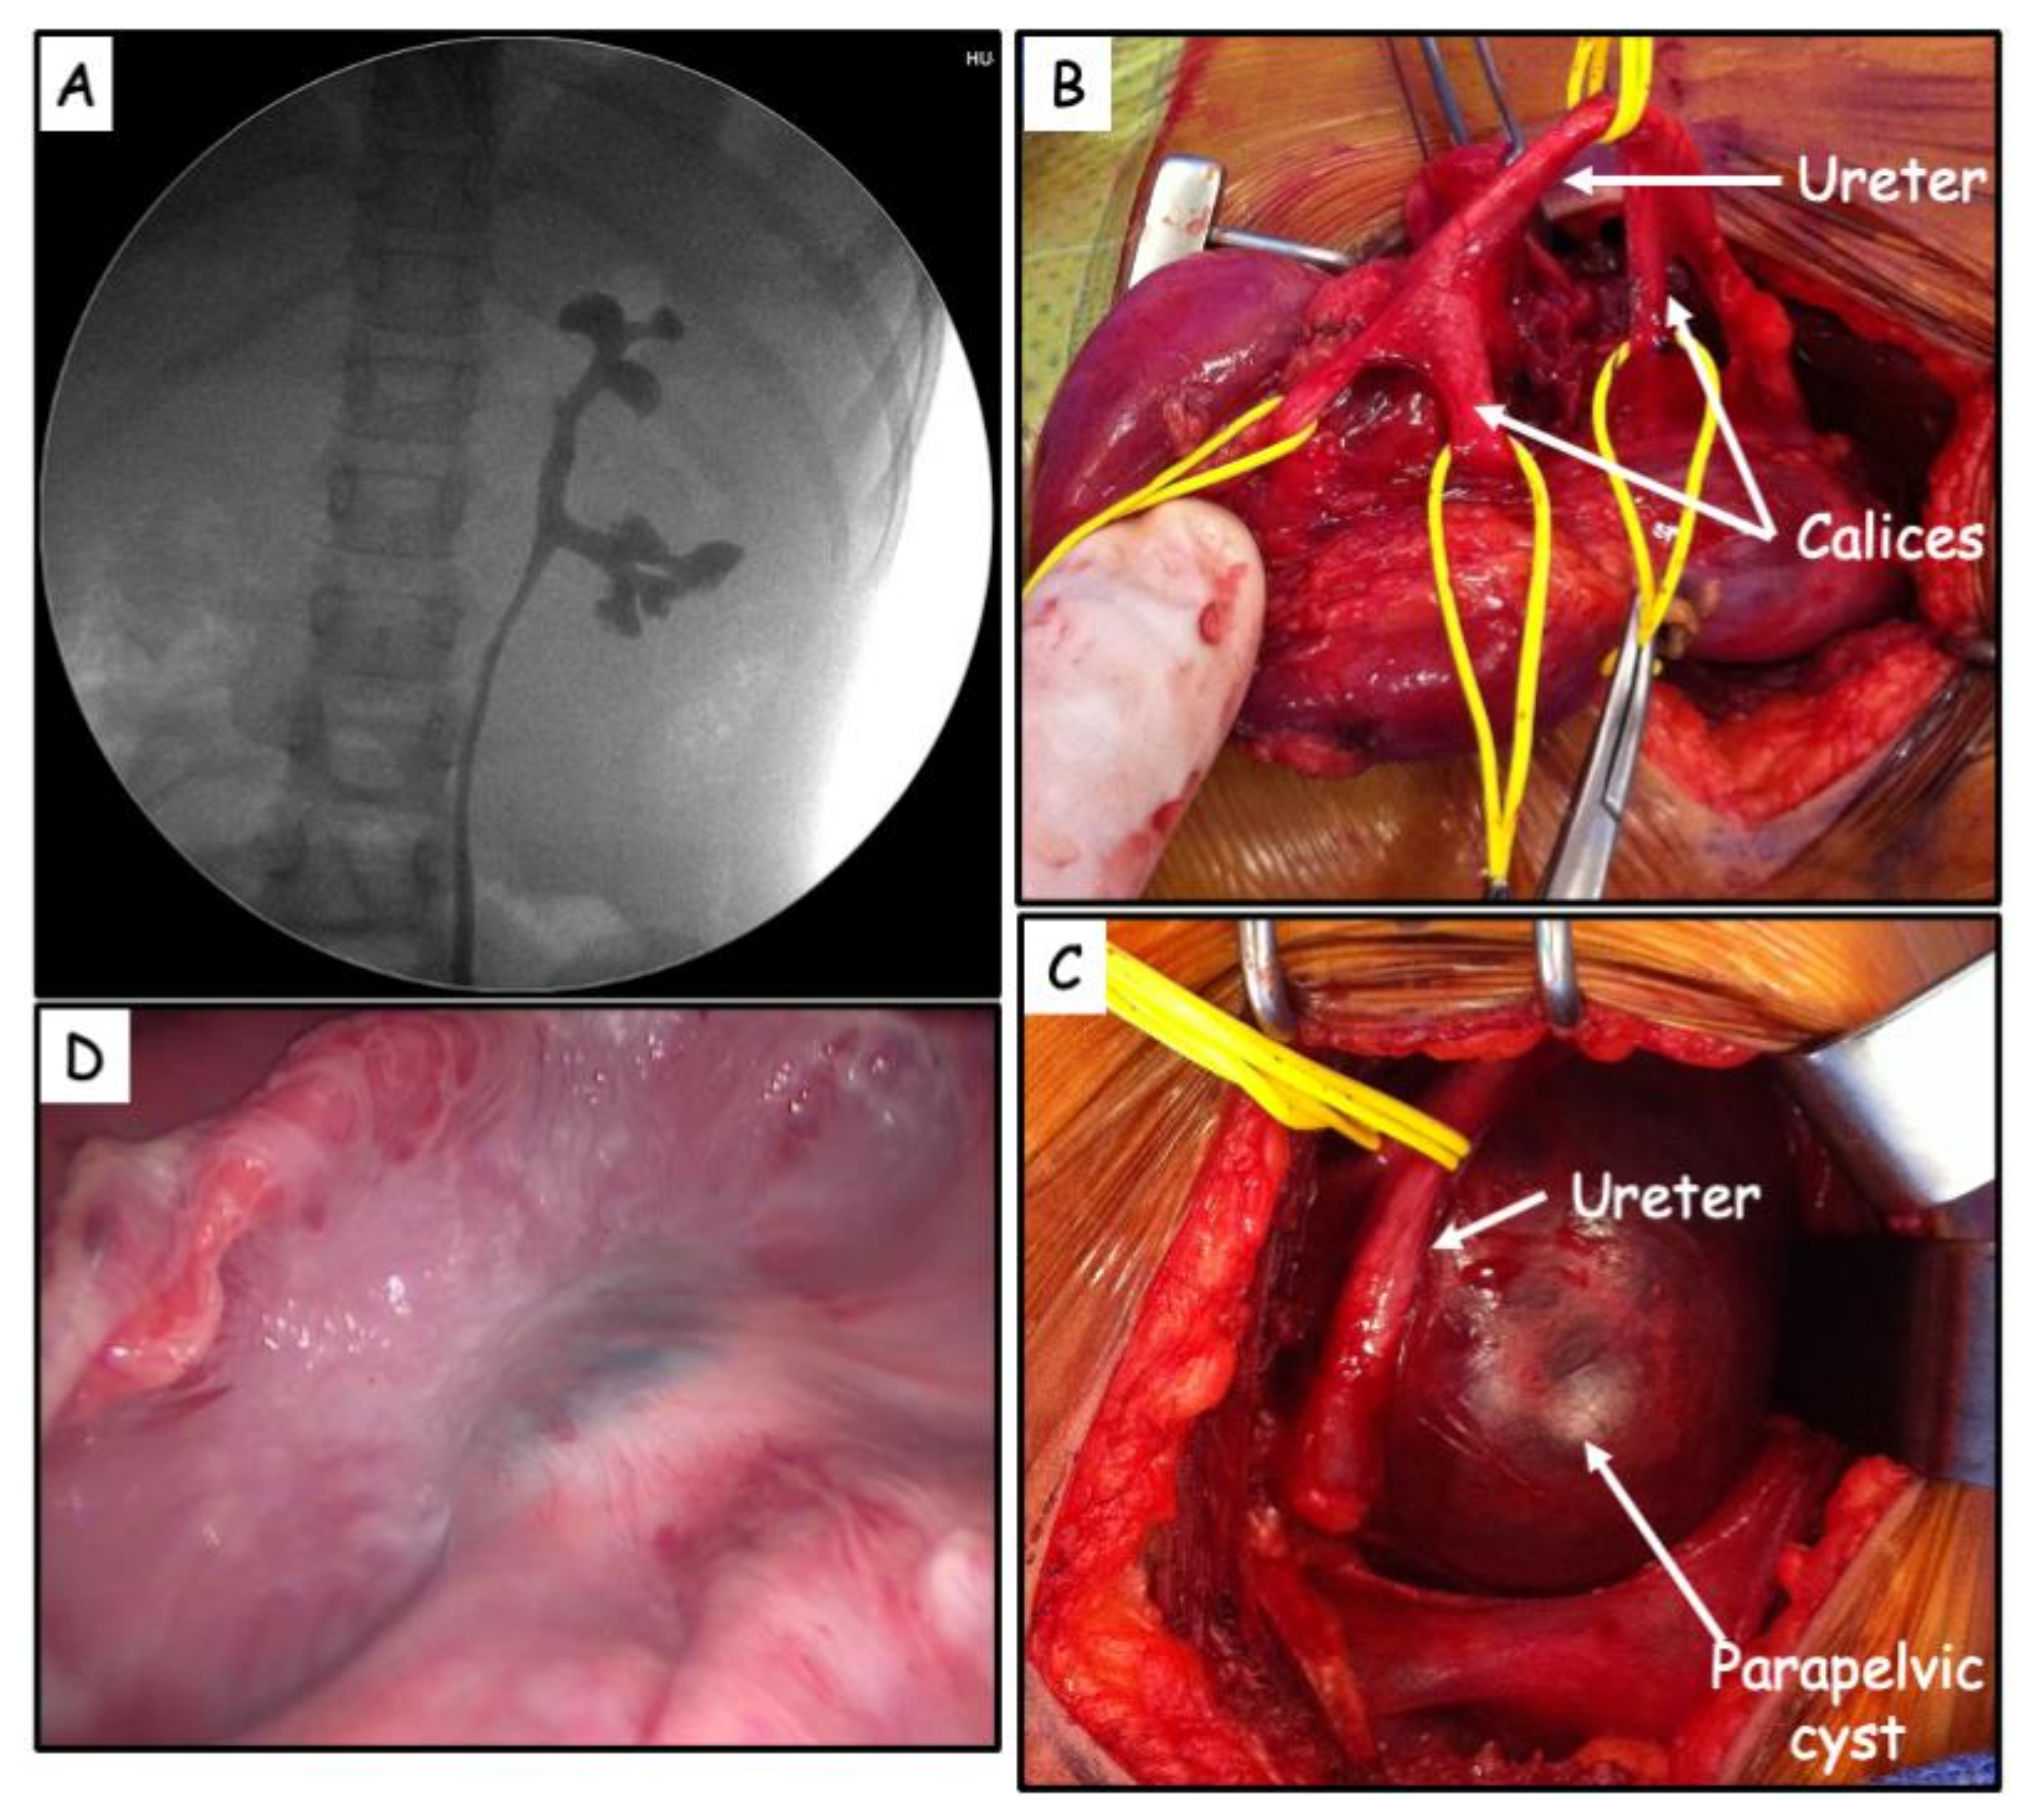

| Case # | Age | Presentation | Renal US | Size (mm) | MRI/CT Scan | Pre-op MAG3 RS | Approach | Preoperative Retrograde Pyelography | Intraoperative Retrograde Pyelography Methylene blue | Procedure | Follow-up (years) | Outcome | Post op MAG3 RS |

|---|---|---|---|---|---|---|---|---|---|---|---|---|---|

| 1-M | 18 months | Abdominal pain Vomiting | Pelvis dilatation | 42 | - | 48% | Subcostal flank incision | - | - | De-roofing | 7 | Asymptomatic | - |

| 2-F | 8 years | Abdominal pain | Pelvis dilatation | 85 | PPC | 38% | Laparoscopy | No pelvicalyceal dilatation | No communication | De-roofing | 4 | Asymptomatic | 51% |

| 3-M | 7 years | Renal colic Vomiting | Cystic mass | 55 | PPC | 21% | Subcostal flank incision | No renal pelvis | - | De-roofing | 5.5 | Asymptomatic | 17% |

| 4-F | 5 years | UTI Abdominal pain | Cystic mass | 60 | PPC | - | Laparoscopy | No renal pelvis | - | De-roofing | 3.5 | Asymptomatic | - |